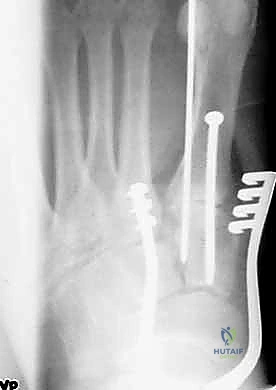

1. الرد المفتوح والتثبيت الداخلي (ORIF - Open Reduction and Internal Fixation)

هذا هو الإجراء الكلاسيكي والأكثر شيوعاً. يهدف إلى إعادة العظام إلى مكانها الطبيعي (الرد) وتثبيتها باستخدام معدات طبية (مسامير، شرائح، أو أسلاك) حتى تلتئم الأربطة والعظام.

خطوات العملية:

1. التخدير: يتم إجراء الجراحة تحت التخدير الموضعي (النصفي) أو العام.

2. الشق الجراحي: يقوم الدكتور هطيف بعمل شق جراحي دقيق (أو شقين) على ظهر القدم للوصول إلى المفاصل المصابة، مع الحرص الشديد على حماية الأعصاب والأوعية الدموية الدقيقة في تلك المنطقة باستخدام مبادئ الجراحة المجهرية.

3. التنظيف والرد: يتم تنظيف المفاصل من أي شظايا عظمية أو أنسجة محشورة تمنع عودة العظام لمكانها. ثم يتم إعادة العظام بحذر شديد إلى محاذاتها التشريحية الدقيقة (القوس الروماني).

4. التثبيت (Fixation): يتم تثبيت العظام باستخدام مسامير معدنية خاصة (Solid or Cannulated Screws) تعبر المفاصل لتثبيتها بإحكام. في بعض الحالات، يتم استخدام شرائح معدنية صغيرة للحفاظ على الاستقرار.

5. مسمار ليزفرانك: الخطوة الأهم هي وضع "مسمار ليزفرانك" (Lisfranc Screw) الذي يمر من العظم المسماري الإنسي إلى قاعدة المشط الثاني، لتعويض وظيفة الرباط الممزق.

6. الإغلاق: يتم إغلاق الشقوق الجراحية بعناية تجميلية ووضع القدم في جبيرة لحمايتها.